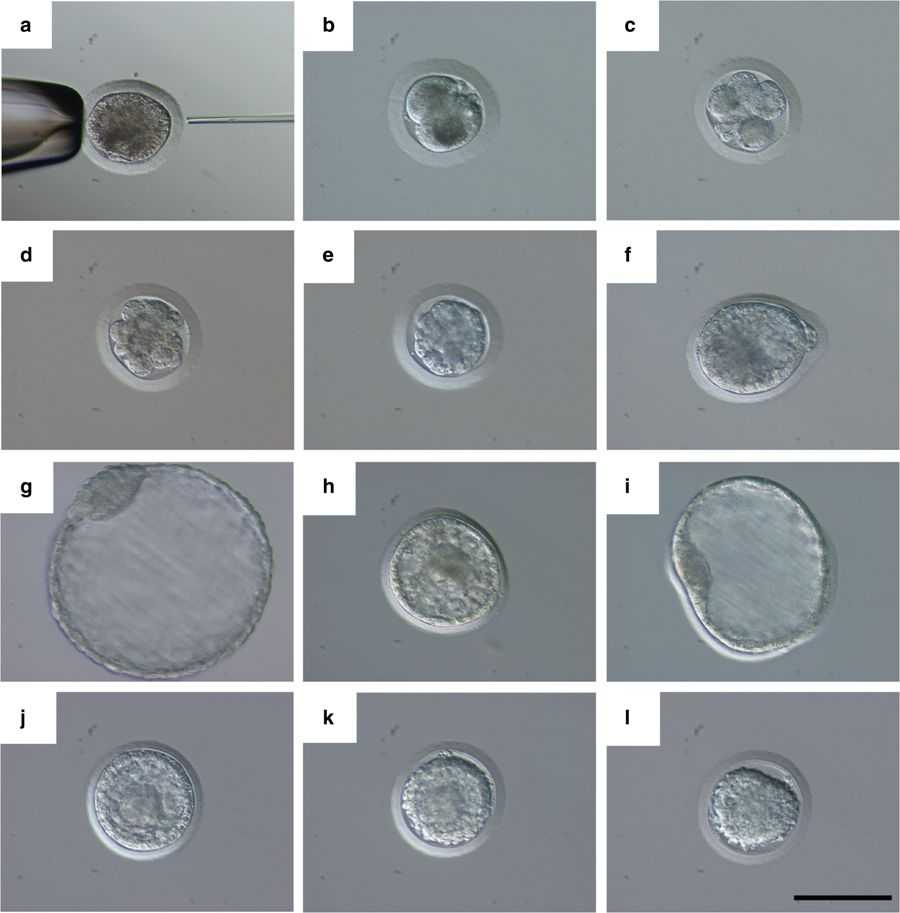

Бластоциста на 5 день — это стадия развития эмбриона, когда он уже начинает разделяться на клетки и приобретает важные структурные особенности. На этом этапе эмбрион представляет собой пузырёк с жидкостью, в котором находятся клетки, будущие части организма. На микроскопических фотографиях эта стадия выглядит впечатляюще, и изучение её позволяет понять, как развивается человеческий организм в самом начале. В этом материале мы собрали информацию о том, что происходит с эмбрионом на 5 день, а также полезные советы для тех, кто заинтересован в этой теме.

Визуально бластоциста на 5 день под микроскопом выглядит как пузырёк с жидкостью и группой клеток, которые постепенно организуются в будущие ткани.

Фотографии бластоцисты на 5 день помогают врачам и исследователям оценить качество эмбриона перед его возможной имплантацией.

Стадия бластоцисты является важной в контексте подготовки к пересадке эмбриона, так как она показывает, что эмбрион готов к дальнейшему развитию.

Микроскопические изображения бластоцисты помогают медицинским специалистам исключить возможные аномалии и выбрать самые здоровые эмбрионы для трансплантации.

Бластоциста и эмбрион 7 дня развития

Для точной диагностики и планирования дальнейших шагов в процессе ЭКО врачи внимательно анализируют бластоцисту, обращая внимание на её форму и состав клеток.